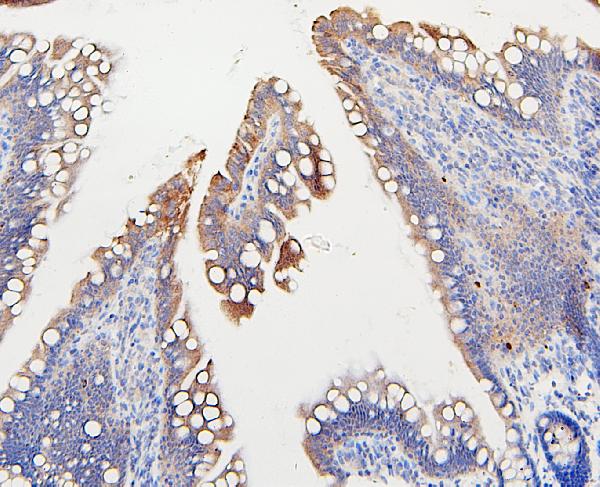

Figure 1. IHC analysis of IFNAR2 using anti-IFNAR2 antibody (A02056-3). IFNAR2 was detected in paraffin-embedded section of human placenta tissues. Heat mediated antigen retrieval was performed in citrate buffer (pH6, epitope retrieval solution) for 20 mins. The tissue section was blocked with 10% goat serum. The tissue section was then incubated with 1microg/ml rabbit anti-IFNAR2 Antibody (A02056-3) overnight at 4°C. Biotinylated goat anti-rabbit IgG was used as secondary antibody and incubated for 30 minutes at 37°C. The tissue section was developed using Strepavidin-Biotin-Complex (SABC)(Catalog # SA1022) with DAB as the chromogen.